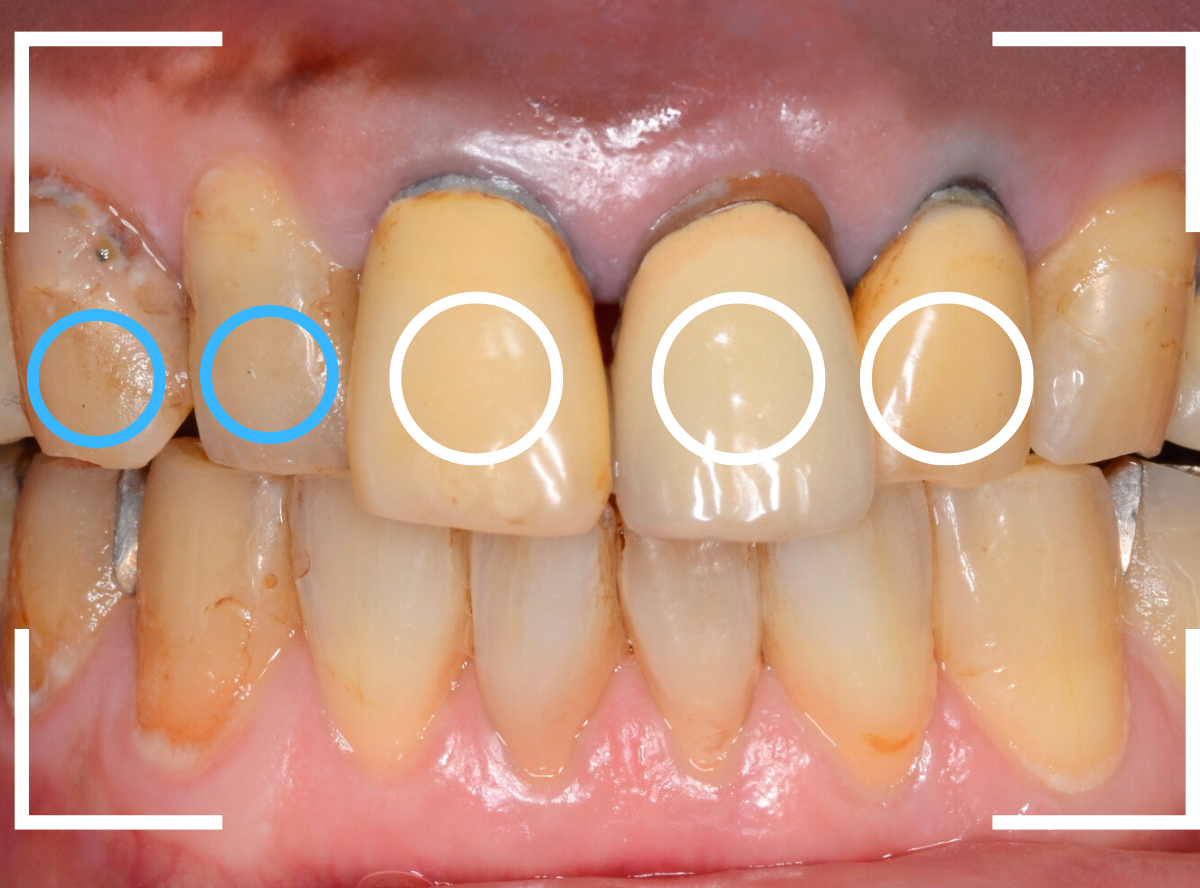

今回は、前歯のさし歯が古くなったので、セラミックで綺麗にしたいというご希望の患者さんです。

患者さんのご希望は白い〇部分の3本でしたが、レントゲン検査をすると隣の2本も虫歯があり、一緒に治療をする事になりました。

左側の2本は虫歯を除去してみないと最終的にどのようにお治しするか何とも言えない状況でしたので、同時に治療しながら最終的な仕上げはご相談、となりました。